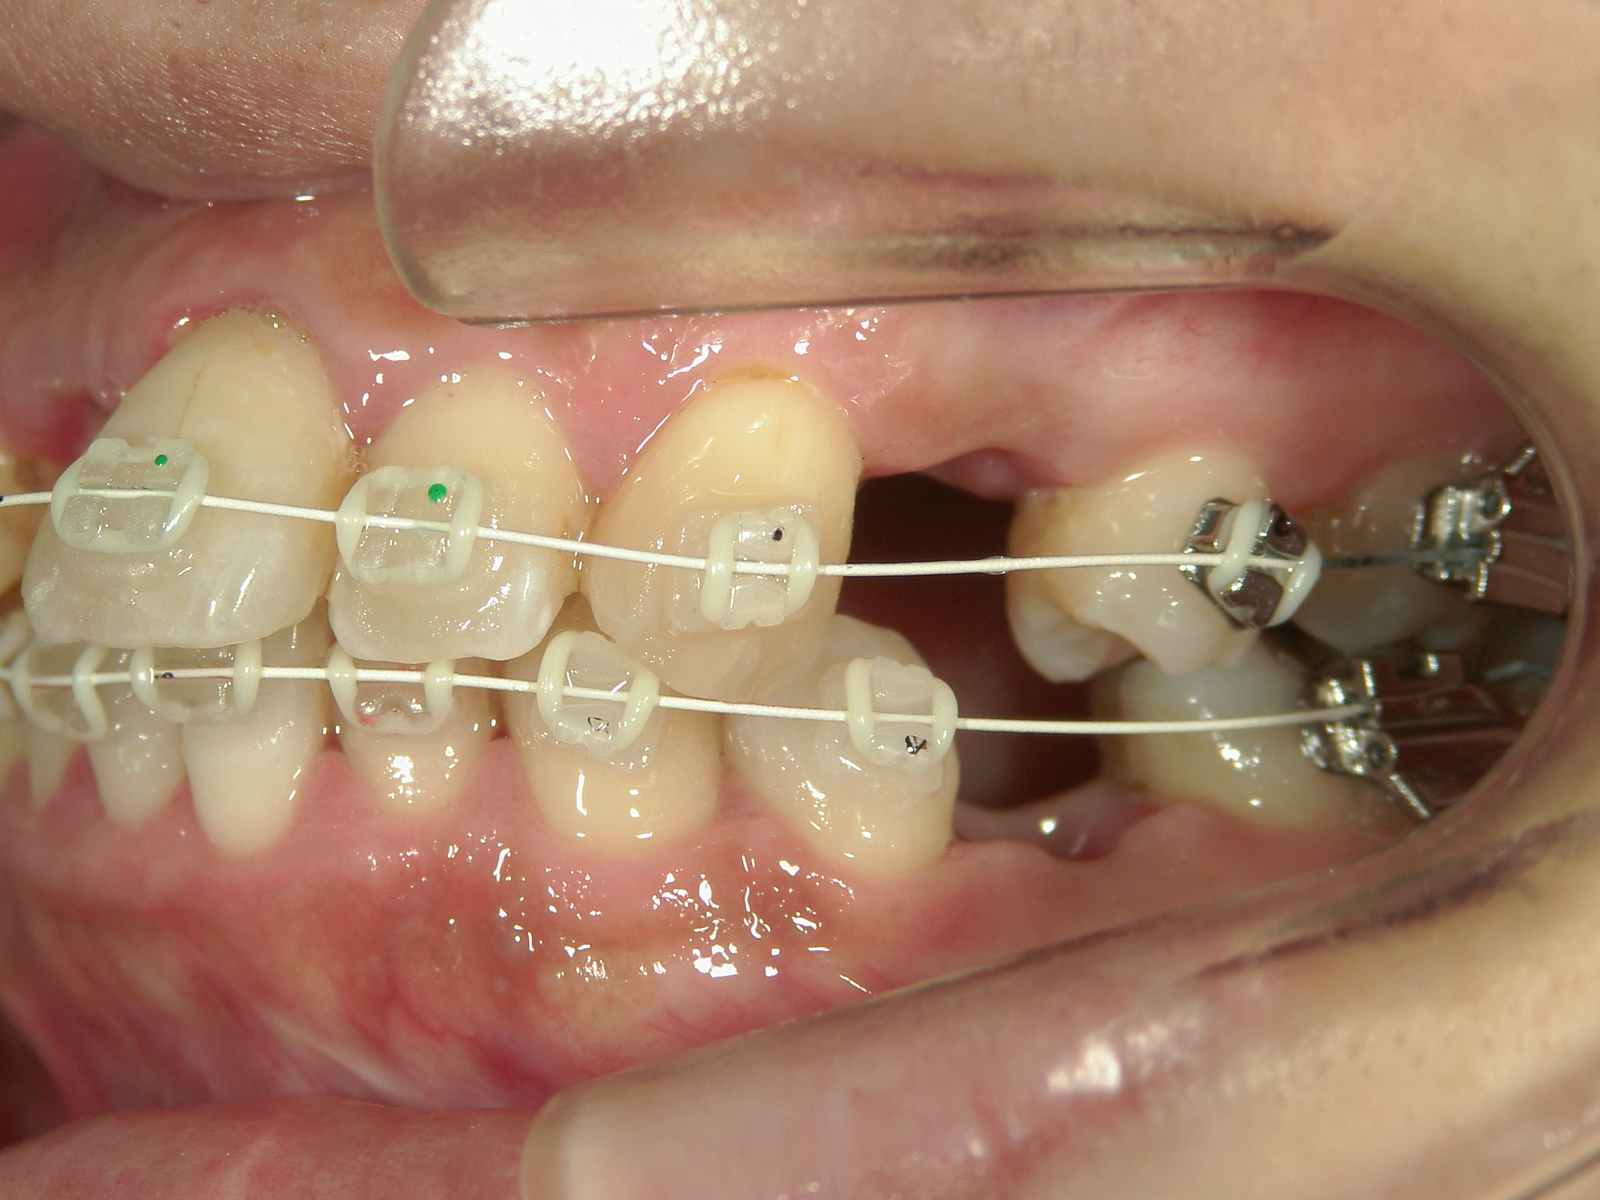

右上中切歯 抜歯後、空隙を閉鎖しました。

歯根の移動後、元々の中切歯の形に硬質レジンで歯冠を形態修正しました。

・抜歯した右上前歯の隣りの歯を抜歯してあいたスペースで移動。

・右上犬歯を移動して、開いたスペースへ移動。

・右上 第一小臼歯を移動して犬歯のスペースへ移動。